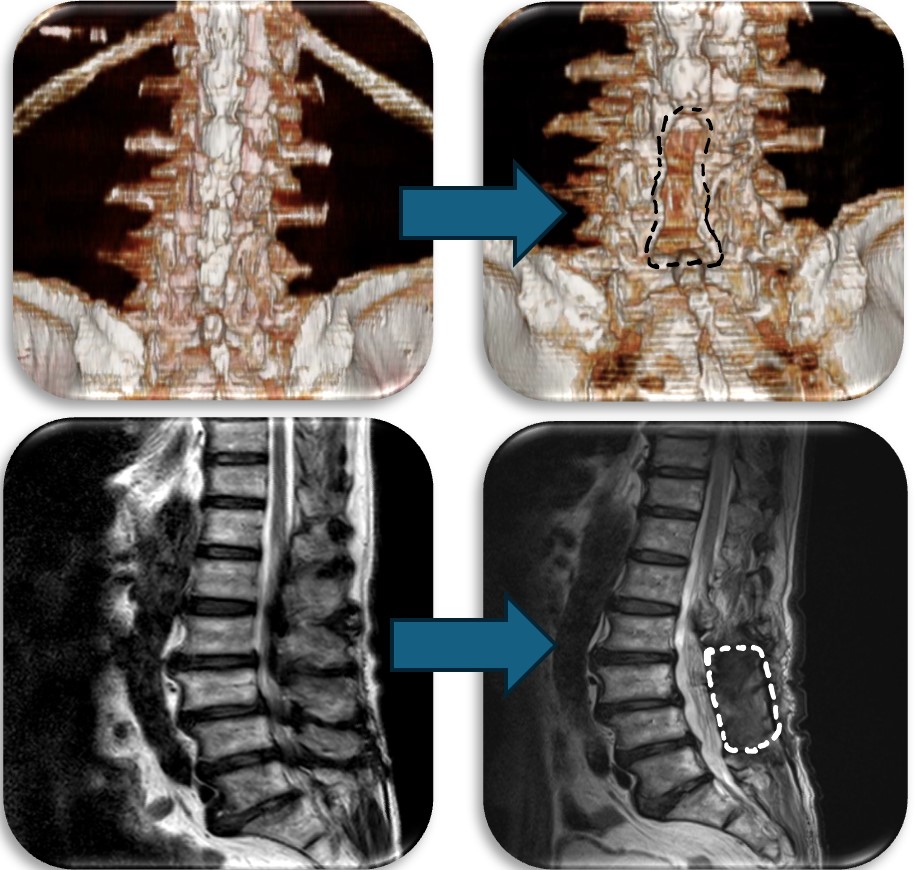

頚部の脊柱管狭窄症に対して、首の後ろから手術する椎弓形成術を行なった症例です。脊柱管と呼ばれる脊髄が通るトンネルの屋根部分にあたる椎弓を縦割し観音開きで広げ、さらに新しい屋根の代わりとなる金属プレートを被せることによって脊柱管を広げます。

腰部の脊柱管狭窄症に対して、腰の後ろから手術する椎弓切除術を行なった症例です。脊柱管と呼ばれる脊髄が通るトンネルの屋根部分にあたる椎弓を切除(点線部分)することによって狭かった脊柱管を広げます。